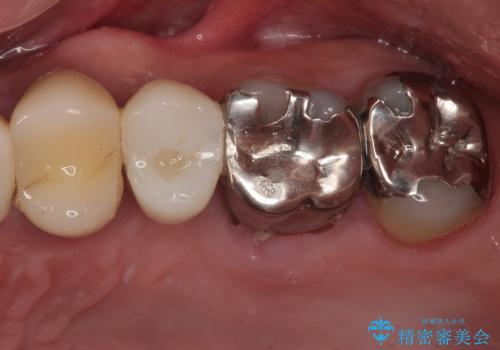

奥歯に虫歯があると言われた セラミッククラウンでキレイで長持ちする歯へ

担当医 榊原康平